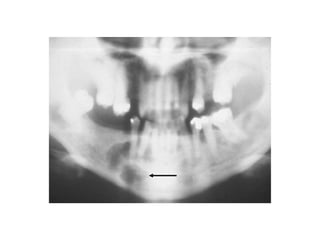

Periapical cemento-osseous dysplasia